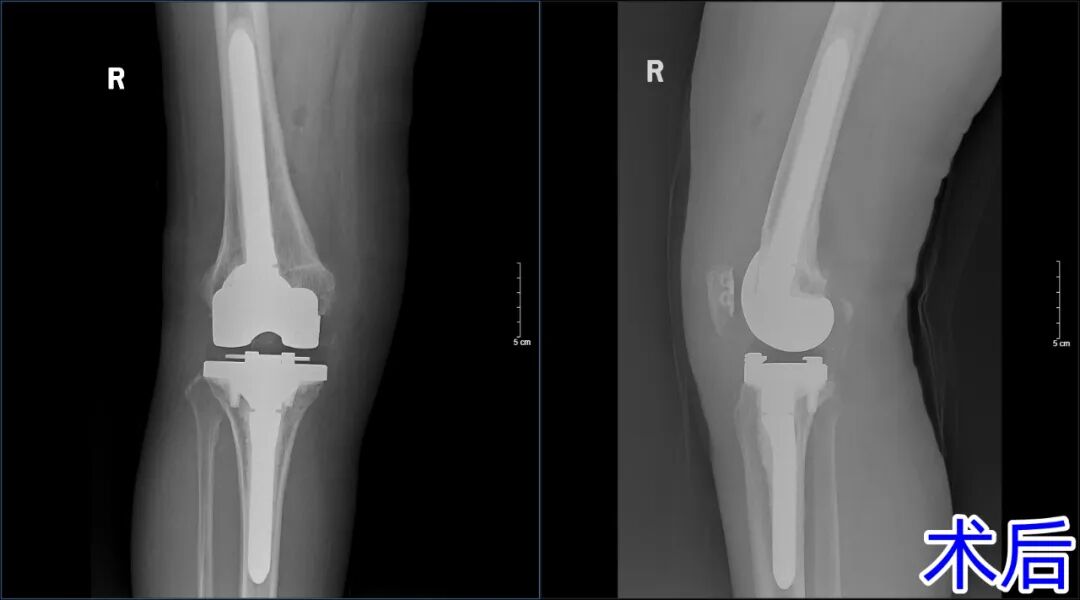

当人工关节出现松动、感染、磨损或位置异常时,需要通过二次手术更换部分或全部假体。相比初次置换,翻修手术面临骨缺损修复、软组织平衡等更高挑战,对主刀医生的经验和技术要求极高。杨学良主任团队迎难而上,在手术室与麻醉科的密切配合下顺利为患者实施手术。

令人欣喜的是,经过医护团队的共同努力,术后第二天患者就能在助行器辅助下行走,一周后已能脱离辅助工具自己行走。每一次手术都是病人的托付,每一例成功都是医学的进步。济南南郊医院骨二科将继续以匠心仁术,为更多患者解除关节病痛,守护老年人的健康晚年!